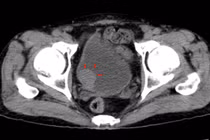

U bàng quang là loại u thường gặp trong các loại u ở đường tiết niệu. Theo thống kê, ung thư bàng quang là bệnh lý đứng thứ hai sau ung thư tiền liệt tuyến thuộc hệ tiết niệu sinh dục.

(khoahocdoisong.vn) - Nhờ phẫu thuật cấp cứu khẩn cấp các bác sĩ bệnh viện Nội Tiết T.Ư đã cứu sống được bệnh nhân bị u bàng quang gây bí tiểu, bàng quang nhiều máu cục, sốc mất máu kèm đường huyết tăng cao...